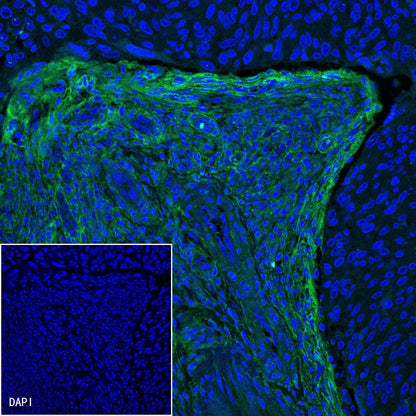

Immunofluorescence

IF shows positive staining in paraffin-embedded human squamous cell lung carcinoma. Anti-PDGFRA+PDGFRB antibody was used at 1/100 dilution (Green) and incubated overnight at 4°C. Goat polyclonal Antibody to Rabbit IgG - H&L (Alexa Fluor® 488) was used as secondary antibody at 1/1000 dilution. Counterstained with DAPI (Blue). Heat mediated antigen retrieval with EDTA buffer pH9.0 was performed before commencing with IF staining protocol.